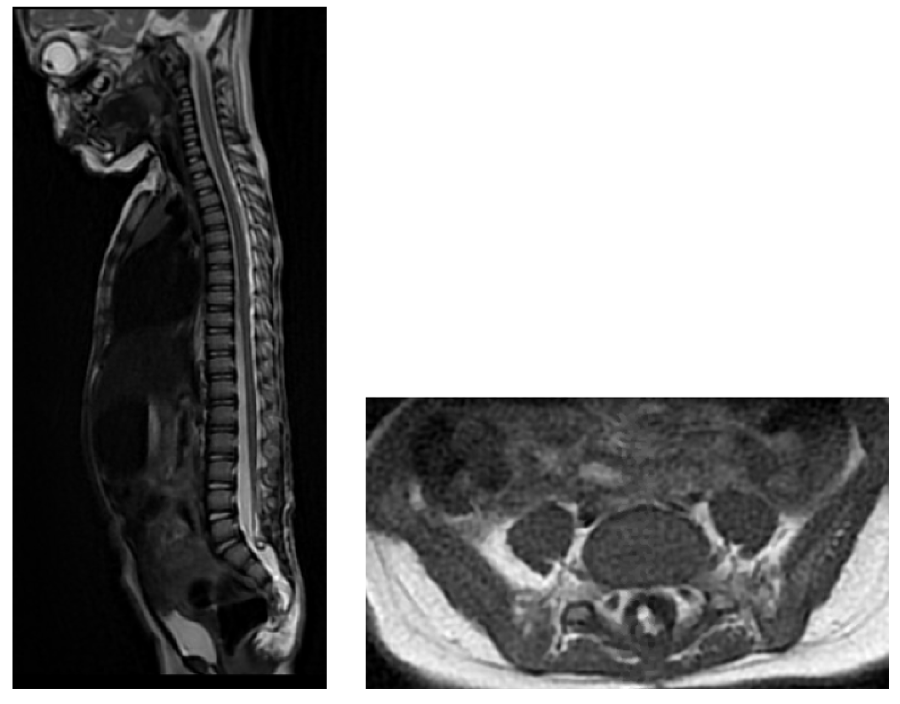

At 1 year and 4 months old, she was admitted to the emergency department for sub-acute loss of walking which had started a month earlier. She also exhibited sudden onset of urinary retention. She was thus transferred to our specialised center for management. Upon arrival, she was moving spontaneously on all-fours. She was able to stand up with support and could walk couple of steps but only with assistance. She had dorsiflexion and eversion weakness on the left greater than the right side with manual muscle testing being under 3/5. She did not respond to tactile stimulation on the left lower limb. Due to the sudden neurological deterioration cerebral and spinal MRI were ordered. The cerebral MRI was normal, and the spinal MRI was remarkable for the appearance of a large syringomyelic cavity extending from T11 to S1 with associated spinal cord edema (figure 1). She thus underwent a detethering surgery with restoration of perimedullary CSF space and near total lipoma resection. At day 1 post-surgery she had complete recovery of motor and sensory functions. Bowel and bladder resumed normal functions at day 2 post-surgery.

Figure 2: MRI findings at subacute worsening showing an extensive syringomyelia A: sagittal T2 B: sagittal T2 CISS) View Figure 2